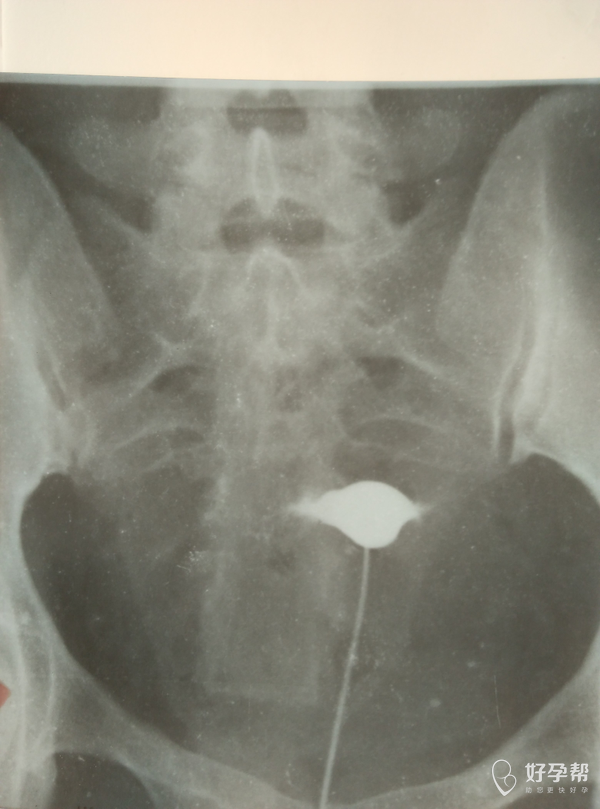

双侧输卵管堵塞做手术有希望吗?谢谢!